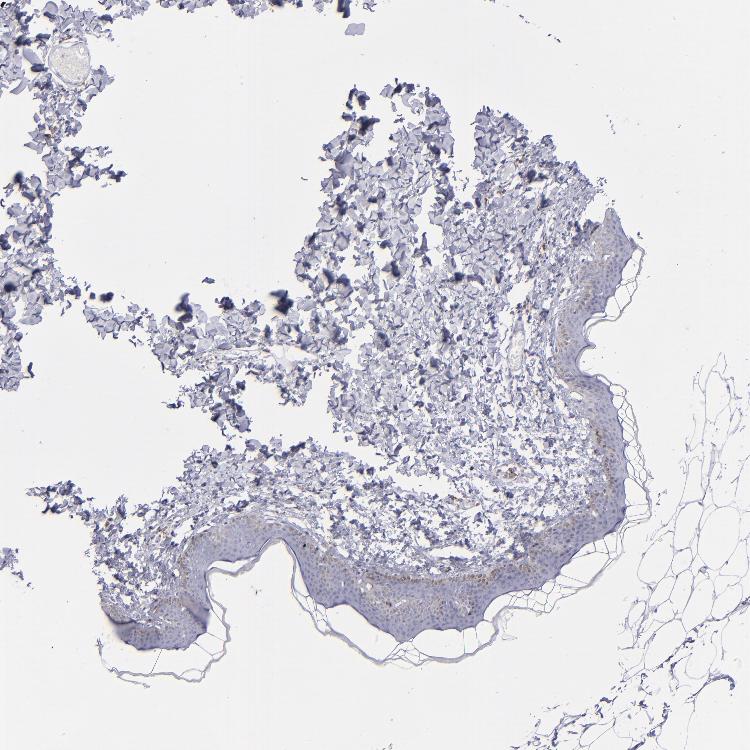

SKIN 1 - Antibody stainingi

Antibody staining in the annotated cell types in the current human tissue is reported as not detected, low, medium, or high, based on conventional immunohistochemistry profiling in selected tissues. This score is based on the combination of the staining intensity and fraction of stained cells.

Each image is clickable and will lead to virtual microscopy that enables deeper exploration of all samples and also displays staining intensity scores, fraction scores and subcellular localization as well as patient and tissue information for each sample.

Antibody HPA069062Antibody CAB002431

Langerhans Not detectedNot detected

Fibroblasts Not detectedNot detected

Keratinocytes Not detectedNot detected

Melanocytes Not detectedNot detected